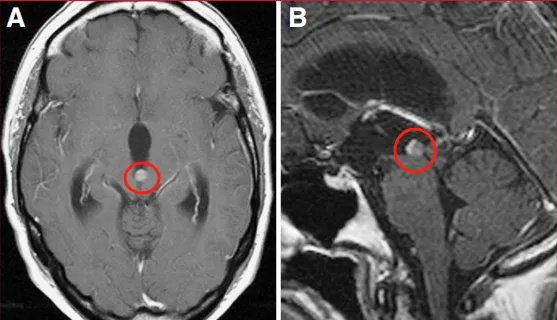

49岁女性,主诉头痛、恶心及呕吐。磁共振成像(MRI)显示一小型、明显强化的占位性病变阻塞中脑导水管,导致三脑室性脑积水(图1)。

经右侧室间孔(Monro孔)行内镜下手术(图A)。术中实现病变全切除(图B)。

术后MRI复查示病灶无残留,脑积水已完全缓解。